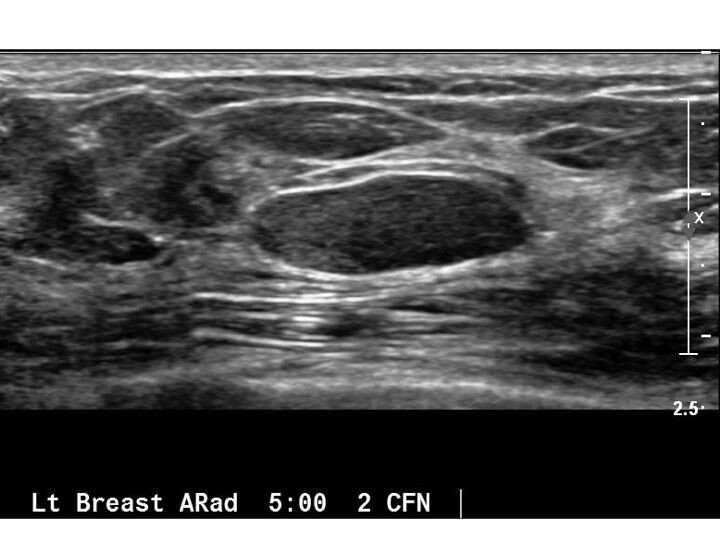

• Киста – это полое образование, заполненное жидкостью. Она представляет собой замкнутую полость в ткани, которая наполнена серозной жидкостью. При пальпации киста обычно более мягкая и подвижная.

• Киста обычно диагностируется с помощью ультразвукового исследования, которое позволяет определить размер и содержимое кисты, а также оценить состояние стенок.